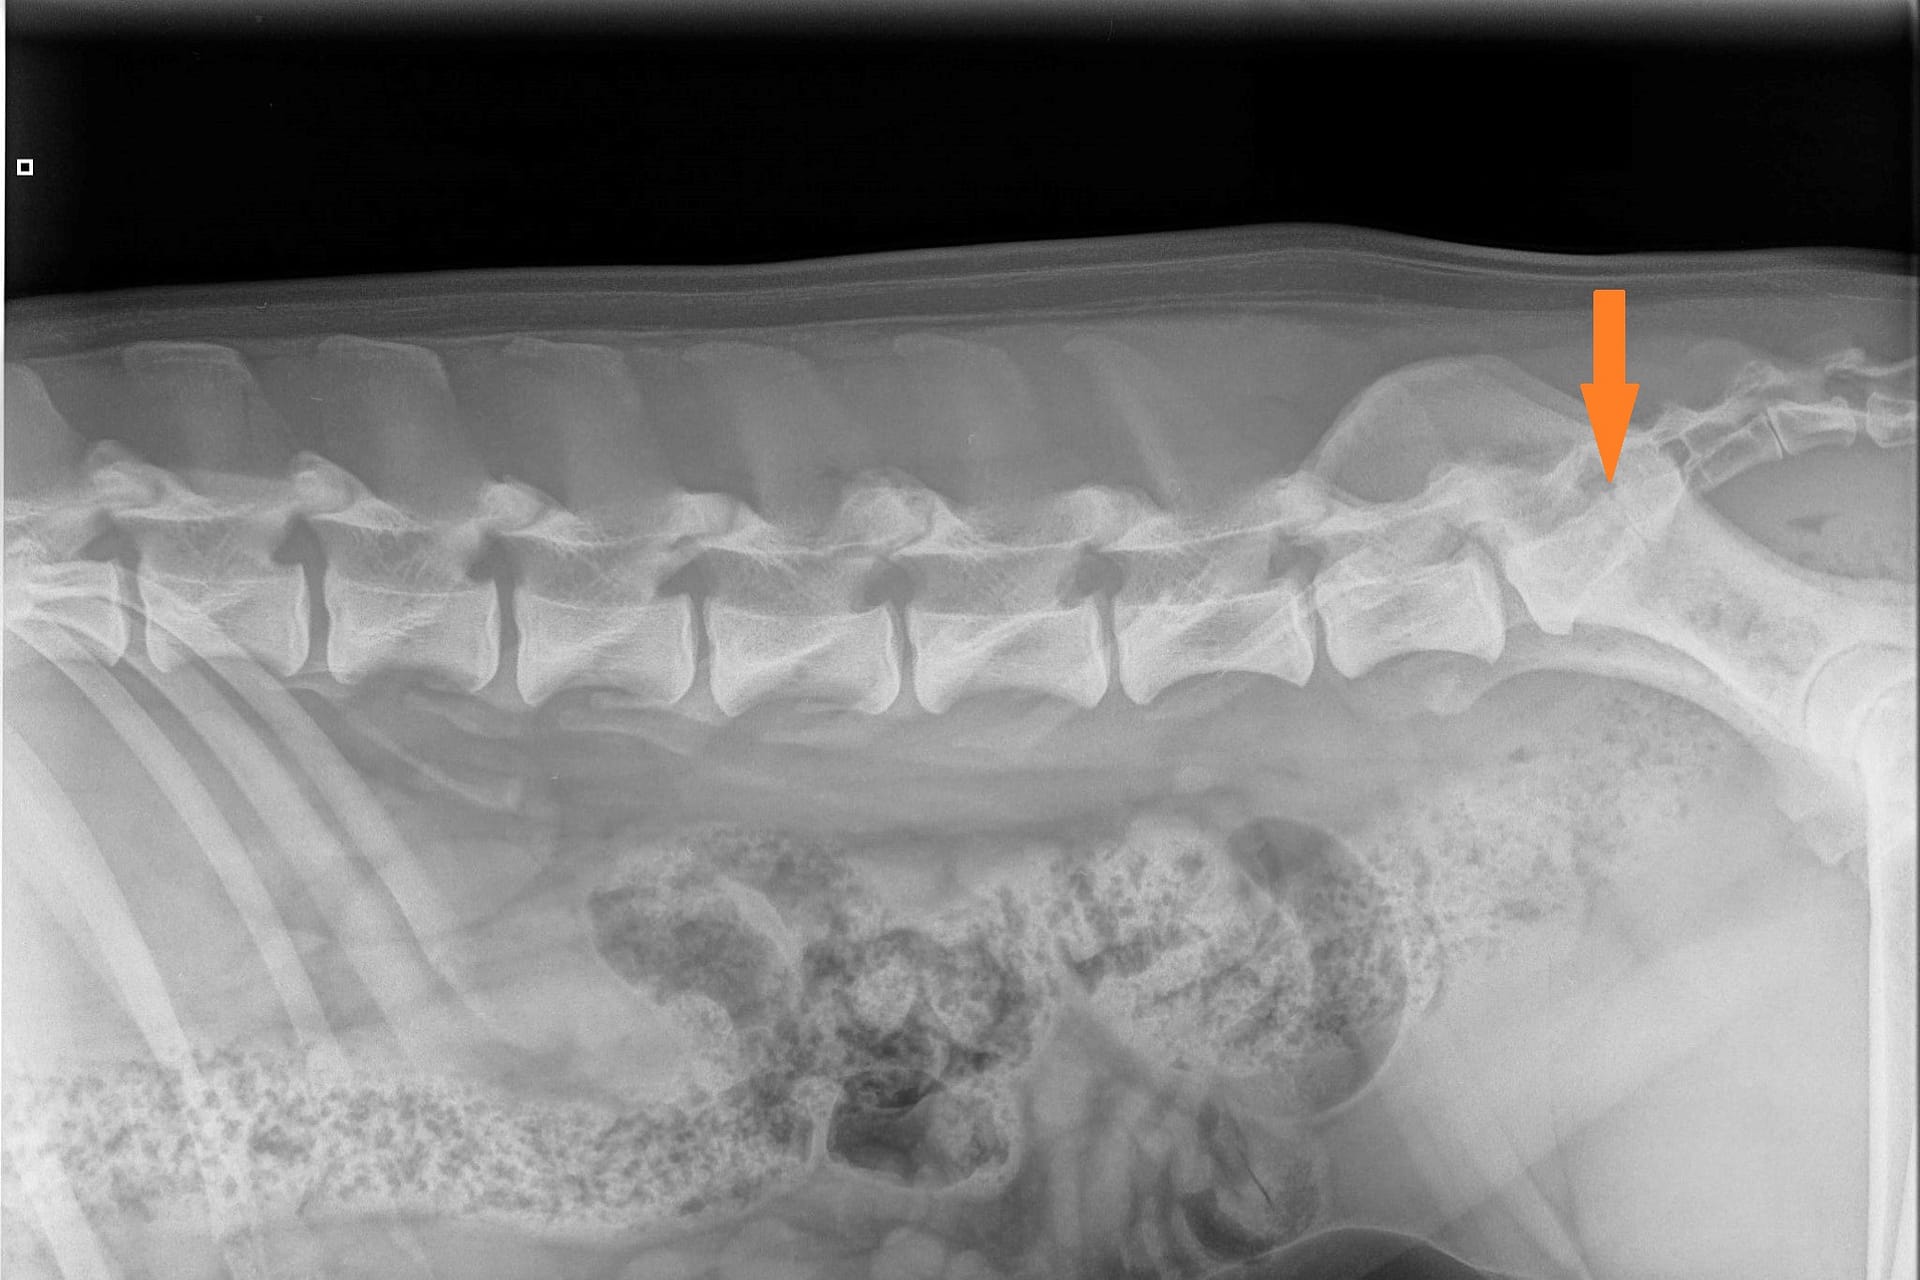

LTV2; symmetrical